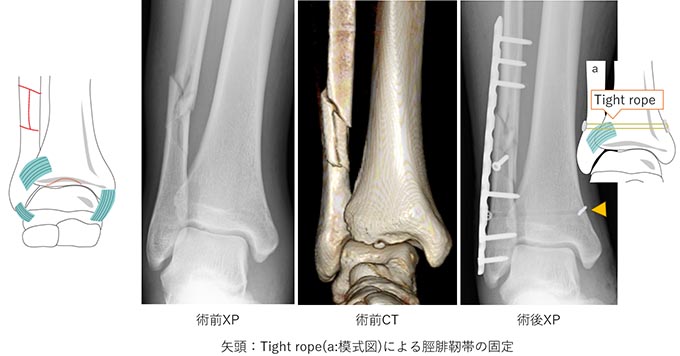

手術の方法は、骨折した部分をもともとの形に整復し、プレートやスクリュー、針金などを用いて固定します(図6−8)。

図8.TypeC骨折

骨だけでなく、脛腓靭帯が損傷し不安定性が強い場合は、スクリューやスーチャーボタン(タイトロープなど)用いて腓骨と脛骨間を固定することもあります。